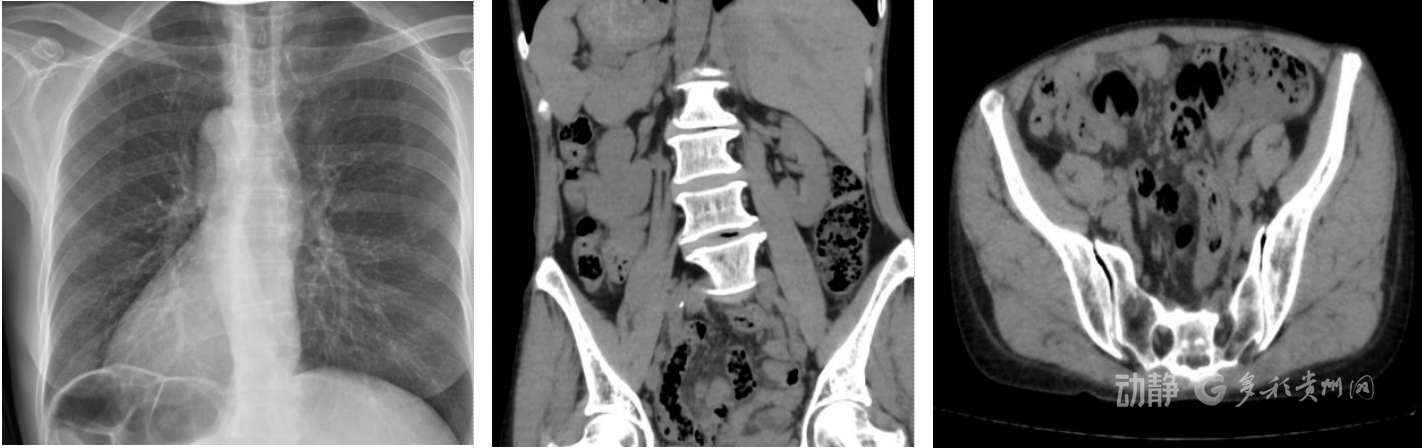

据了解,该患者起初感到上腹部隐痛,之后疼痛转移并固定于左下腹,且持续加重。接诊医生查体发现,其左下腹有明显压痛和反跳痛,虽症状类似阑尾炎,但阑尾通常位于右侧。这一矛盾引起了医生的高度警惕。经询问得知,患者曾被告知是“镜面人”。紧急CT检查证实,其心脏、肝脏、脾脏、胃肠道等全部内脏位置反位,左下腹可见发炎肿大的阑尾,最终确诊为急性阑尾炎。

全内脏反位是一种先天性解剖变异,发生率仅约几万分之一。这类患者的内脏位置与正常人呈镜像对称,如同照镜子,因此俗称“镜面人”。虽然多数不影响日常生活,但在患病时,症状往往出现在非常规位置,极易造成误诊,延误治疗可导致阑尾穿孔、腹腔感染等严重后果。